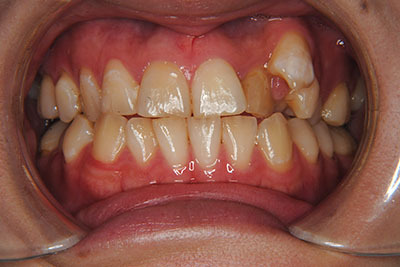

①主訴:左上八重歯を治したい。

②診断名:AngleⅠ級叢生

お口の中を診ますと、左上第二小臼歯が歯列の内側に生え、左上犬歯のスペースは全くない八重歯となっていました。検査結果から骨格的な不正はなく。上奥歯が前にずれたかみ合わせで前歯は合っていて出っ歯ではないので左右1本ずつ歯列からはみ出した状態であることがわかりました。上の奥歯を横の歯1本分後ろにずらすことは困難なので、右上中側に生えている第二小臼歯と八重歯である左上犬歯の次の歯=第一小臼歯の2本を抜歯し治療しました。